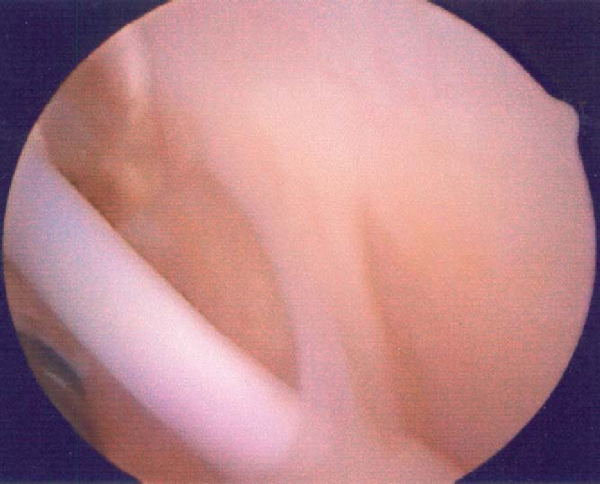

There are many more unusual lesions of the shoulder that may or may not require stabilization. Incorporation of all or part of the biceps into the rotator cuff is a normal variant (

Fig. 7-12

), just like the Buford complex, hypermobile superior labrum, and absent anterior labrum. Before a lesion is repaired, it is incumbent on the surgeon to review the injury, the symptoms, and the physical examination findings to see whether they match the pathologic process that is being viewed. If the mechanism is sufficient to produce the pathologic process being visualized, and the pathologic lesion can produce the symptoms the patient is complaining of, repair is warranted. Elimination of the symptoms after repair may be the only confirmation that the surgeon has performed the correct operation.